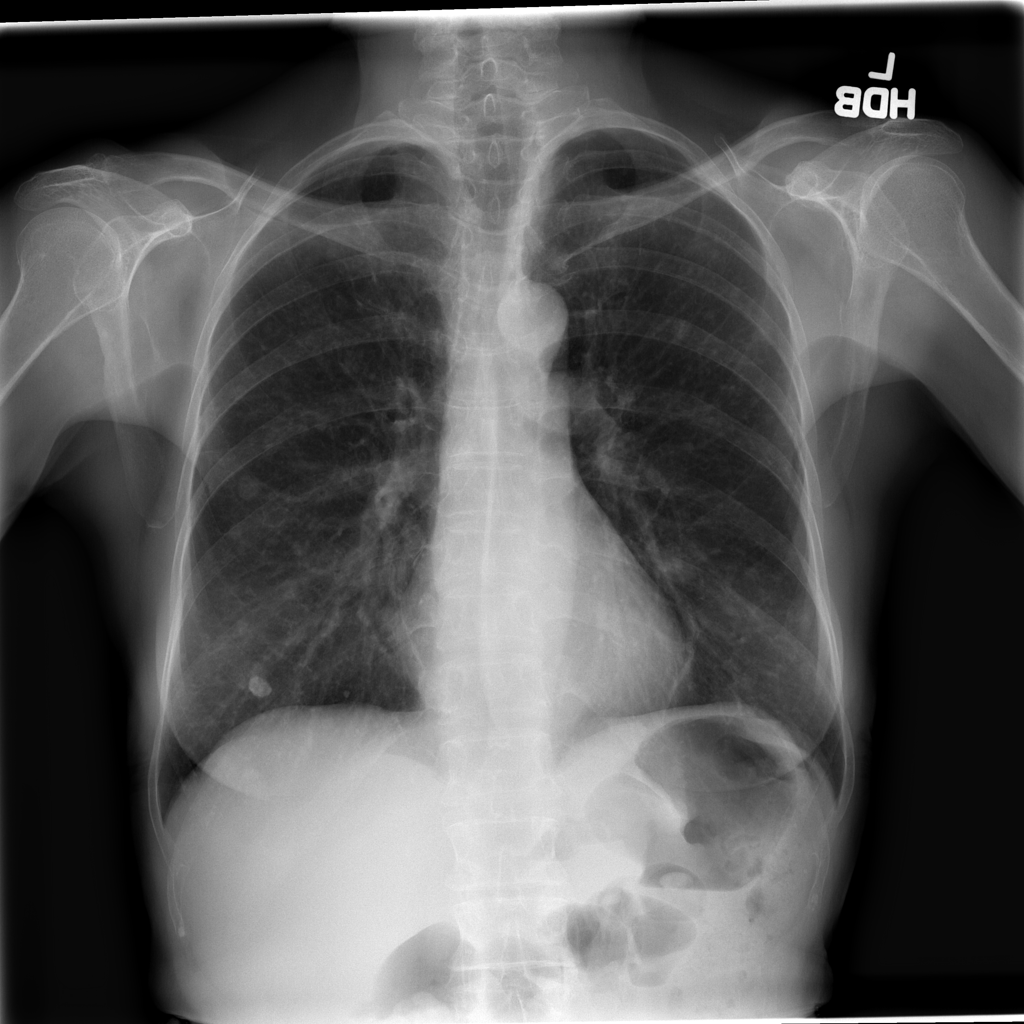

PAT-C9A4 · IMG-000Nodule

PAT-C9A4 · IMG-000

AP